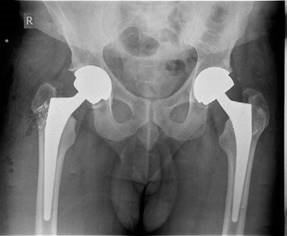

Figure 2.10 Anteroposterior (AP) radiograph left metal-on-metal (MOM) hip and right ceramic large jumbo hip arthroplasty.

There is also concern of tantalum residue within the joint space found in the majority of conversions. Although there is no catastrophic wear seen in studies there is the potential for accelerated joint damage in the medium to long term. EXAMINER : These are his radiographs. He had a large jumbo head MOM performed on the left side and a large ceramic jumbo head THA performed on the right side. Do you have any worries? (Figure 2.10.) CANDIDATE : The BOA released a statement after the annual conference at Torquay in 2011 reporting a higher than anticipated early failure rate for large jumbo head MOM hips. Concern was expressed regarding the trunnion at the ‘Morse’ taper where the large diameter metal head attaches to the stem. Various examples were shown of damage from either wear or corrosion or both resulting in either loosening of the acetabular component, loosening of the femoral component or a metal reaction with necrosis and soft tissue damage. As such its use should now be avoided. Excluding the ASR implant theses devices have a reported revision or impending revision rate of 12–15% at 5 years. EXAMINER : What about follow-up? CANDIDATE : This should be as per BHS guidelines for MOM bearing surfaces, yearly for the first 5 years and probably for life. Pain in this group of patients should be taken seriously and investigated appropriately with cobalt chromium levels and an MRI scan of the hip looking for any local reaction/ tissue necrosis/presence of pseudotumour. EXAMINER : What about the other ceramic hip? CANDIDATE : There are some worries again regarding the trunnion, where the large ceramic head attaches to the stem which may be the source of excessive wear or corrosion, leading again to early failure, although the evidence is not as strong. Endnotes 1. If you initially miss a subtle AVN spot diagnosis it is extremely difficult to recover the viva especially if the candidates before and after you spot it without prompting.